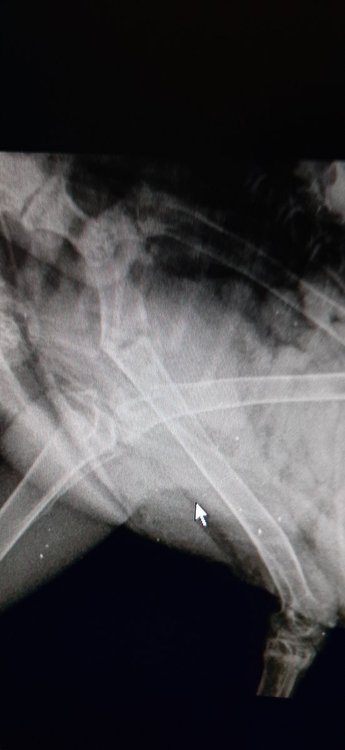

Сделала рентген.(если плохо видно,то могу попросить у вета огиринал перекинуть).Местный ветеринар сказал,что кость почти срослась и всё нормально должно быть в будущем.

20200603_185141.jpg